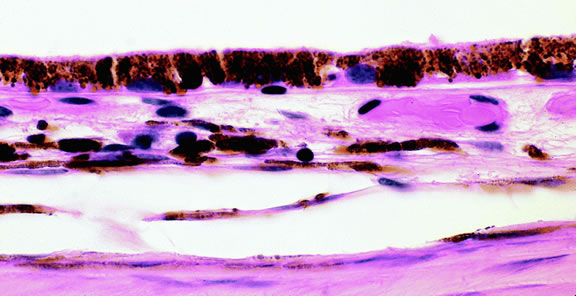

Lymphoma

Although non-Hodgkin's lymphoma often affects the orbit and conjunctiva, intraocular involvement by lymphoma is relatively rare and occurs in two basic ways. First, patients who have widely disseminated systemic lymphoma may develop secondary ocular involvement whose typical manifestation is uveal infiltration. Second, in the variant of central nervous system (CNS) lymphoma that has been called primary lymphoma of the CNS and retina, the vitreous characteristically is involved and the uvea is spared. The latter entity also has been called vitreous large cell lymphoma or ocular “reticulum cell sarcoma.”205–208 In addition to the vitreous, the lymphoma cells also infiltrate the retina, and typically collect between Bruch's membrane and the retinal pigment epithelium, forming solid yellowish RPE detachments, which are highly suggestive of the diagnosis. This rare variant of primary CNS lymphoma should be suspected in older patients who have chronic vitritis that is unresponsive to therapy. Cytologic examination of diagnostic vitrectomy specimens reveals a highly cellular and extensively necrotic infiltrate that contains atypical lymphocytes with prominent nucleoli and protrusions of the nuclear membrane (Fig. 53). The significance of elevated vitreous interleukin 10 levels as a diagnostic marker for lymphoma is controversial.209,210

Fig. 53. Primary central nervous system lymphoma, vitreous. Diagnostic vitrectomy specimen contains large atypical lymphocytes, necrotic lymphoid cells, and nuclear debris. Lymphoma cells in inset have nuclear membrane protrusions and prominent nucleoli. Main figure, Millipore filter. (Hematoxylin-eosin, × 250.)